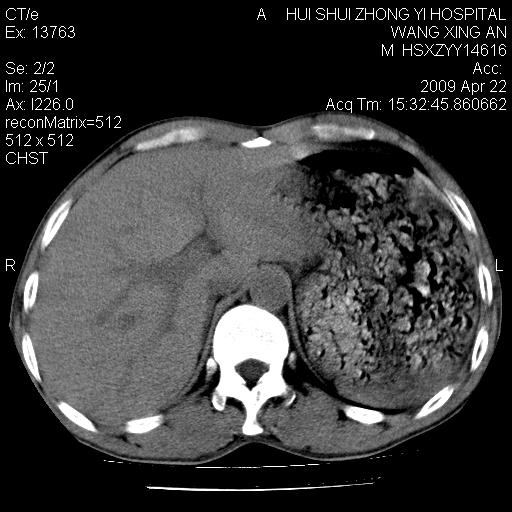

标题: CT19534:患者男、46岁咳嗽、胸痛半月。 [打印本页]

标题: CT19534:患者男、46岁咳嗽、胸痛半月。

右侧中心性肺癌并下叶肺不张,双肺及纵隔淋巴结转移,右侧胸腔积液

1、右下肺中央型肺癌并右肺转移,右肺下叶不张。(肿块围绕右肺下叶支气管生长,致管腔闭塞右肺下叶不张;右肺有结节影)。

2、右侧胸腔积液。

1、右下肺中央型肺癌并右肺转移,右肺中下叶不张。(右肺有结节影)。胸骨转移

1。右下肺中央型肺癌并肺转移,右肺下叶不张。(两肺都有结节影)。

1)右肺中间段支气管癌并右肺下叶肺不张。2)右肺上叶、两肺下叶背段感染性病变。3)右侧少量胸腔积液。